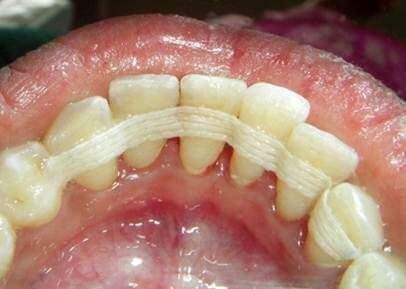

Extra-coronal Splints (“extra” – outside; “coronal” – crown): With this approach, splinting materials are attached to a group of teeth generally by bonding to the enamel, thus making them more rigid.